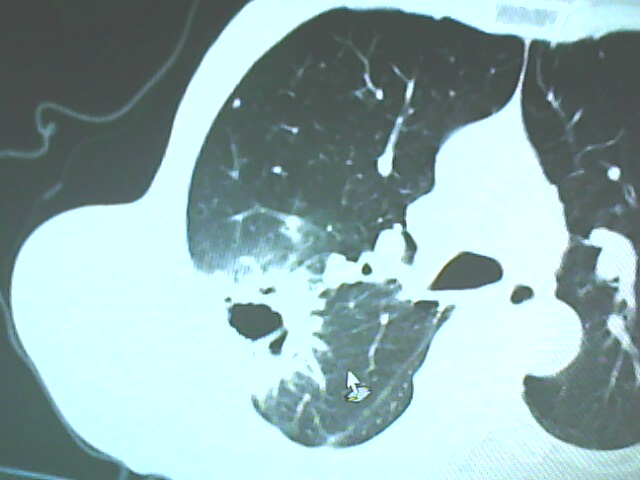

患者,男,66岁,以咳嗽、咳痰伴胸痛来就诊。

胸片提示右上肺占位病变。请各位老师看看ct。

考虑癌性空洞可能性大,空洞内壁不规则,病灶周围模糊,分叶、有毛刺

空洞内壁不规则,病灶周围模糊,分叶、毛刺呈日光放射状,突然截断,支持考虑癌性空洞

考虑右肺上叶后段周围型肺癌并癌性空洞形成。

考虑癌性空洞可能性大,内壁不规则,洞壁薄厚不均呈结节状突起,边缘模糊,分叶,毛刺

右上肺后段肺癌:

典型癌性空洞(偏心性,壁厚薄不均,内壁不光整),周围毛刺较僵硬,且有刺突征和血管聚集征